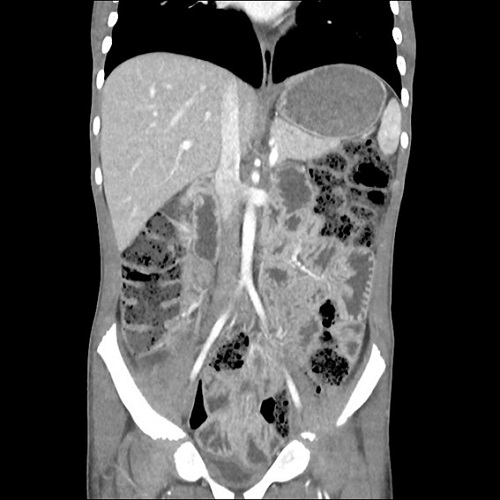

Se completó el estudio etiológico con diversas pruebas complementarias. En la ecografía intestinal inicial se observó engrosamiento difuso de asas, sin claros estigmas de afectación estructurada y adenopatías de carácter reactivo (Figura 1). En el TC abdominal, los hallazgos fueron muy similares (Figura 2). El estudio microbiológico resultó negativo. Para esclarecer el proceso, se realizó una endoscopia alta y baja, macroscópica e histológicamente normales, salvo una atrofia vellositaria total en el duodeno, sin datos de inflamación crónica ni de apoptosis.

| Figura 1. Paciente de 8 años. Crisis celíaca. Ecografía abdominal: engrosamiento difuso de asas intestinales y numerosas adenopatías, de carácter reactivo |

El desafío suele estar en el diagnóstico diferencial, ya que, como se ha comentado, en muchos casos es la CC es la primera manifestación de esta enfermedad. Además, la CC comparte expresión clínica con otros cuadros, tales como una enfermedad inflamatoria intestinal (EII) o una enteropatía autoinmune4. En nuestro caso, y pese a no existir afectación estructurada de asas intestinales en la ecografía, nos vimos en la obligación de realizar un estudio endoscópico completo. Los hallazgos histológicos nos permitieron excluir tanto la EII como la enteropatía autoinume.